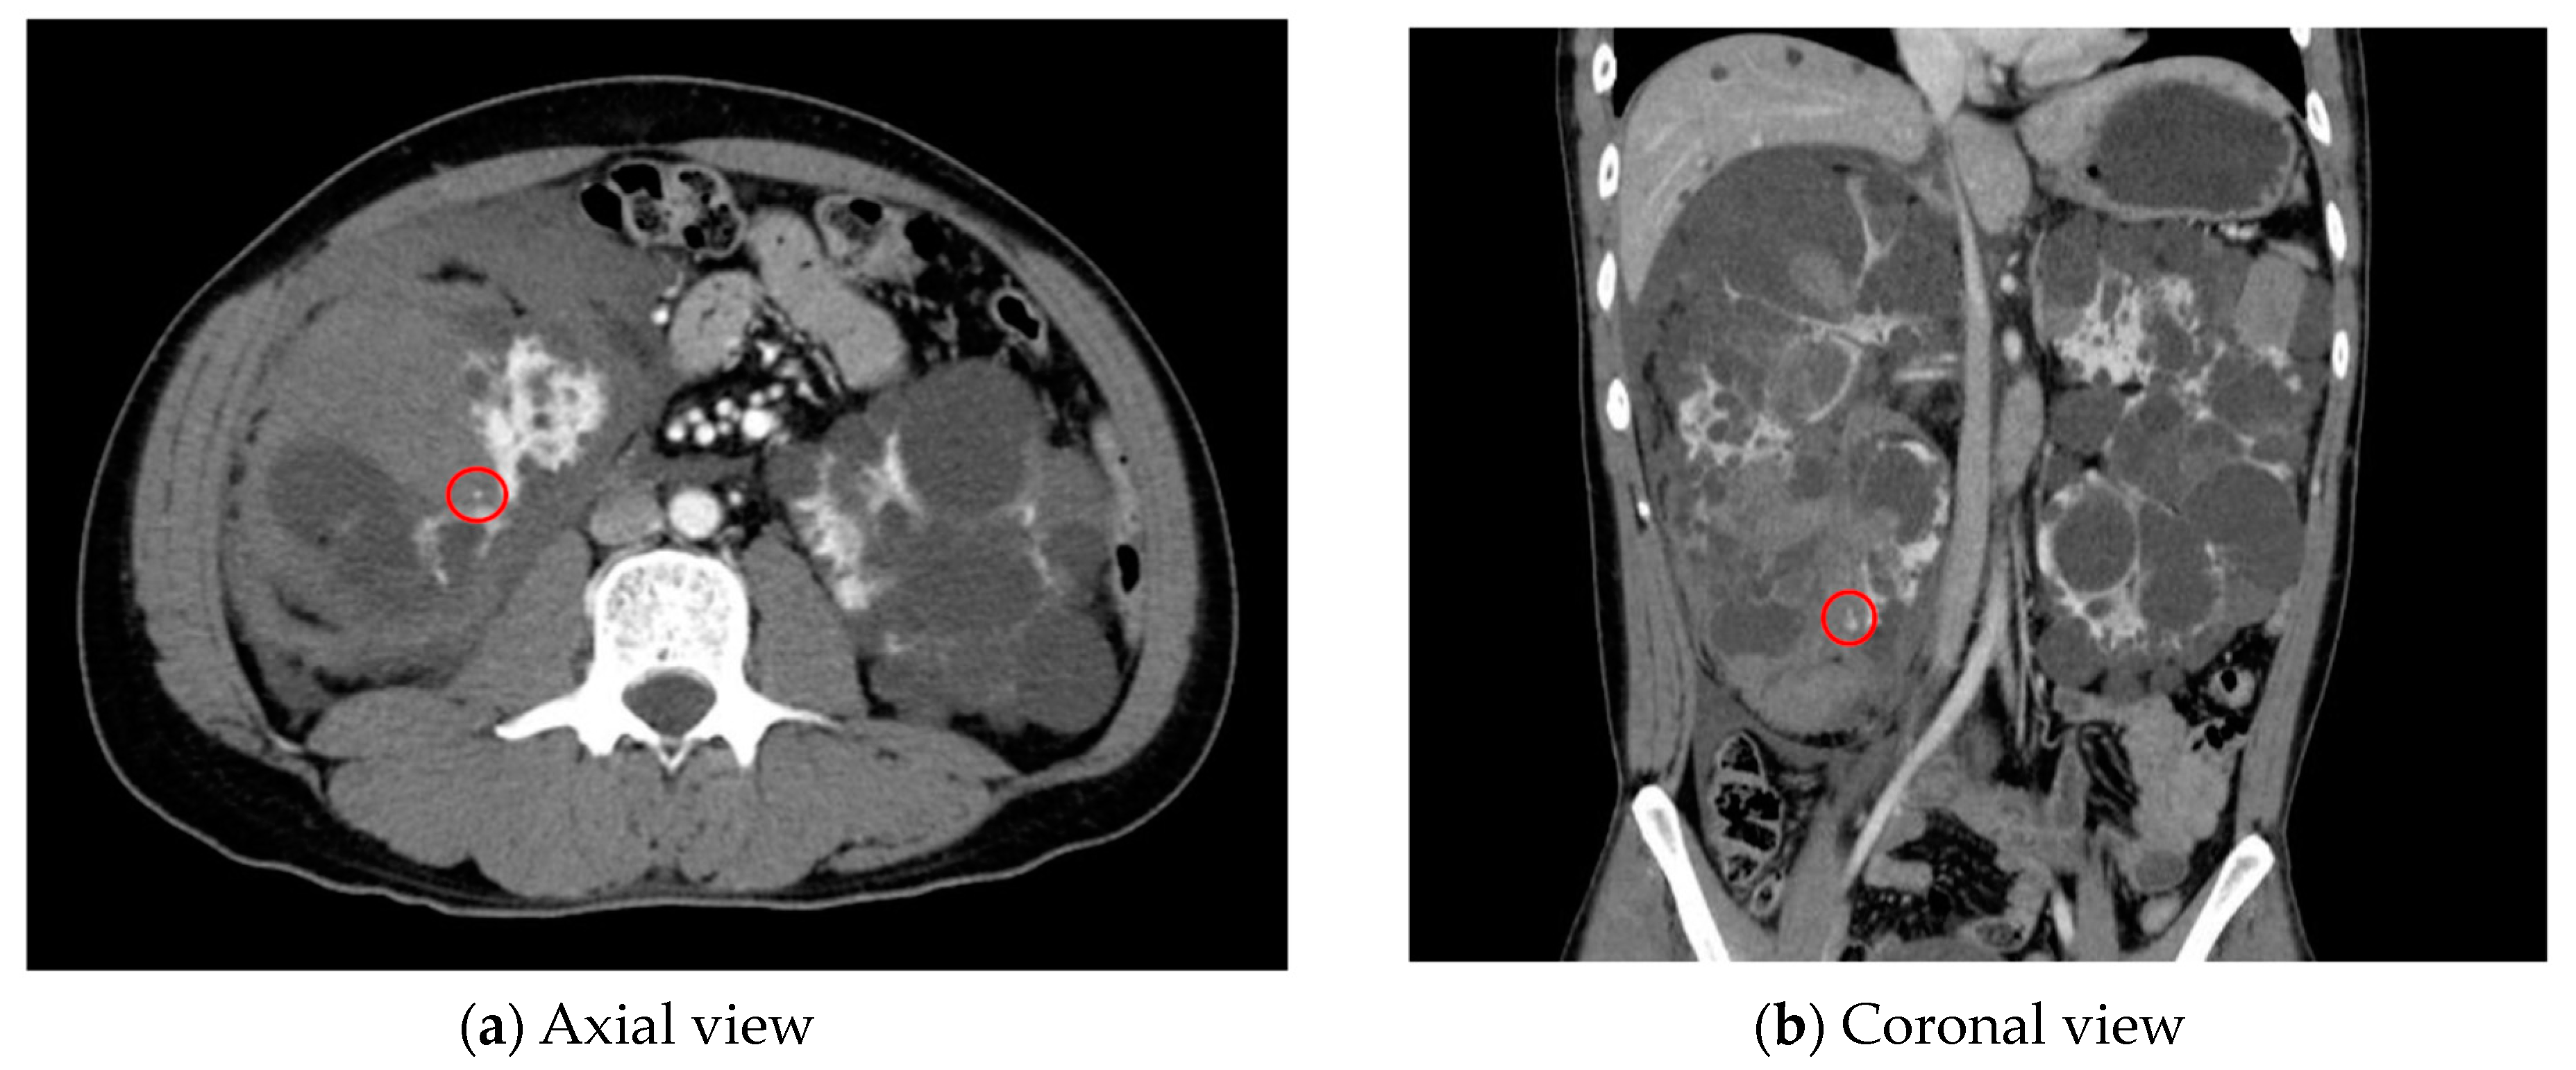

- AI for Image Analysis: AI-based image analysis algorithms can enhance the detection and diagnosis of extravasation events in imaging studies, such as ultrasound, MRI, and CT. These algorithms can automatically identify subtle signs of extravasation, assist healthcare providers in interpreting the imaging findings, and facilitate a timely intervention. This suggestion is subsequently extended as a separate discussion.

- Albano, D.; Benenati, M.; Bruno, A.; Bruno, F.; Calandri, M.; Caruso, D.; Cozzi, D.; De Robertis, R.; Gentili, F.; Grazzini, I.; et al. Imaging side effects and complications of chemotherapy and radiation therapy: A pictorial review from head to toe. Insights Imaging 2021, 12, 76. [Google Scholar] [CrossRef] [PubMed]